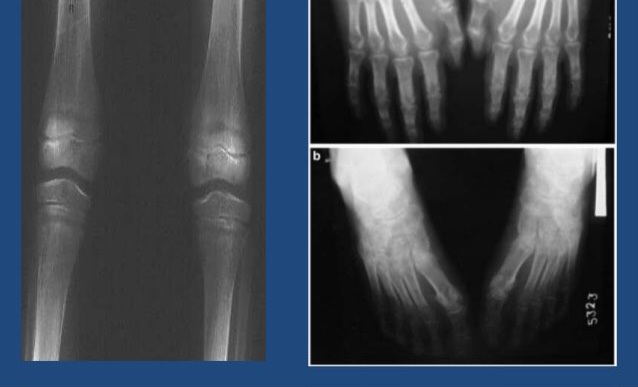

هشاشة العظام غالبًا ما تكون "مرضًا صامتًا" يظهر فجأة بعد حدوث كسر في العظام.

ولكن نقص هرمون الأستروجين في فترة انقطاع الطمث يؤدي تدريجيًا إلى فقدان كثافة العظام وزيادة خطر الكسور.

تعد هشاشة العظام من المشكلات الصحية المهمة للنساء المغربيات بعد انقطاع الطمث، والوعي بها خطوة ضرورية للكشف المبكر والعلاج.